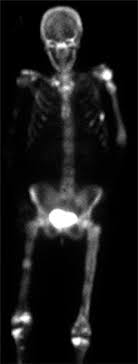

Breast Cancer Wikipedia from upload.wikimedia.org Cancer in bone can cause intermittent or progressively severe localized bone pain where the cancer is in the bone. Sometimes, bone metastasis causes no signs and symptoms. The pain is often described as a dull or sharp throb to the bone or area surrounding the bone. Bone complications are a concern for people with bone metastases as they can cause pain and may lead to loss of mobility, impacting quality of life. I was just looking at a bone scan from february. If the bone has already broken, surgery is usually done to put a steel support over the broken part of the bone. I keep feeling like if i sit up straighter or stand straighter it will feel better but, it doesn't. Depending on where the tumor is, it might be possible to feel a lump or mass.

The pain is from structural damage to the bones and inflammation caused by cancer cells. Usually bone met pain is described as constant or recurring and generally as a dull ache that is difficult to relieve by shifting position. Some women also have dense, fibrous breast tissue. It's one tiny spot, does not feel muscular, is not a dull ache rather a sharp pain. This gradually progresses to a persistent ache or an ache that comes and goes, which continues at night and when resting. Most women notice a lump in the breast or armpit as a first sign of breast cancer, while lung cancer may present itself as frequent coughing and shortness of breath. Bone cancer generally causes extreme fatigue, bruising, and lethargy. A lump or swelling in your breast bone or collar bone area; People with bone metastases are at risk of serious bone complications such as bone fractures (breaks), spinal cord compression and bone pain. The bone pain is described as aching, throbbing, stabbing, and excruciating. For instance, lung cancer that spreads to the bone is made of lung cancer cells. What does bone mets pain feel like? Bone complications are a concern for people with bone metastases as they can cause pain and may lead to loss of mobility, impacting quality of life.

Five Common Sign Symptoms Of Breast Cancer Cancerconnect from news.cancerconnect.com For more than half of women who develop stage iv breast cancer, the bones are the first site of metastasis. Early on, the pain may only occur at night, or when you are active. Bone complications are a concern for people with bone metastases as they can cause pain and may lead to loss of mobility, impacting quality of life. There are different types of primary bone cancers, like osteosarcoma and ewing sarcoma. Pain caused by bone cancer usually begins with a feeling of tenderness in the affected bone. A study published in current oncology in 2006 indicates that breast cancer metastasis can lead to the development of cancerous lesions of the humerus, the upper arm bone 1. A cancerous lump may feel rounded, soft, and tender and can occur anywhere in the breast. Bone pain can cause a dull or deep ache in a bone or bone region (e.g., back, pelvis, legs, ribs, arms).